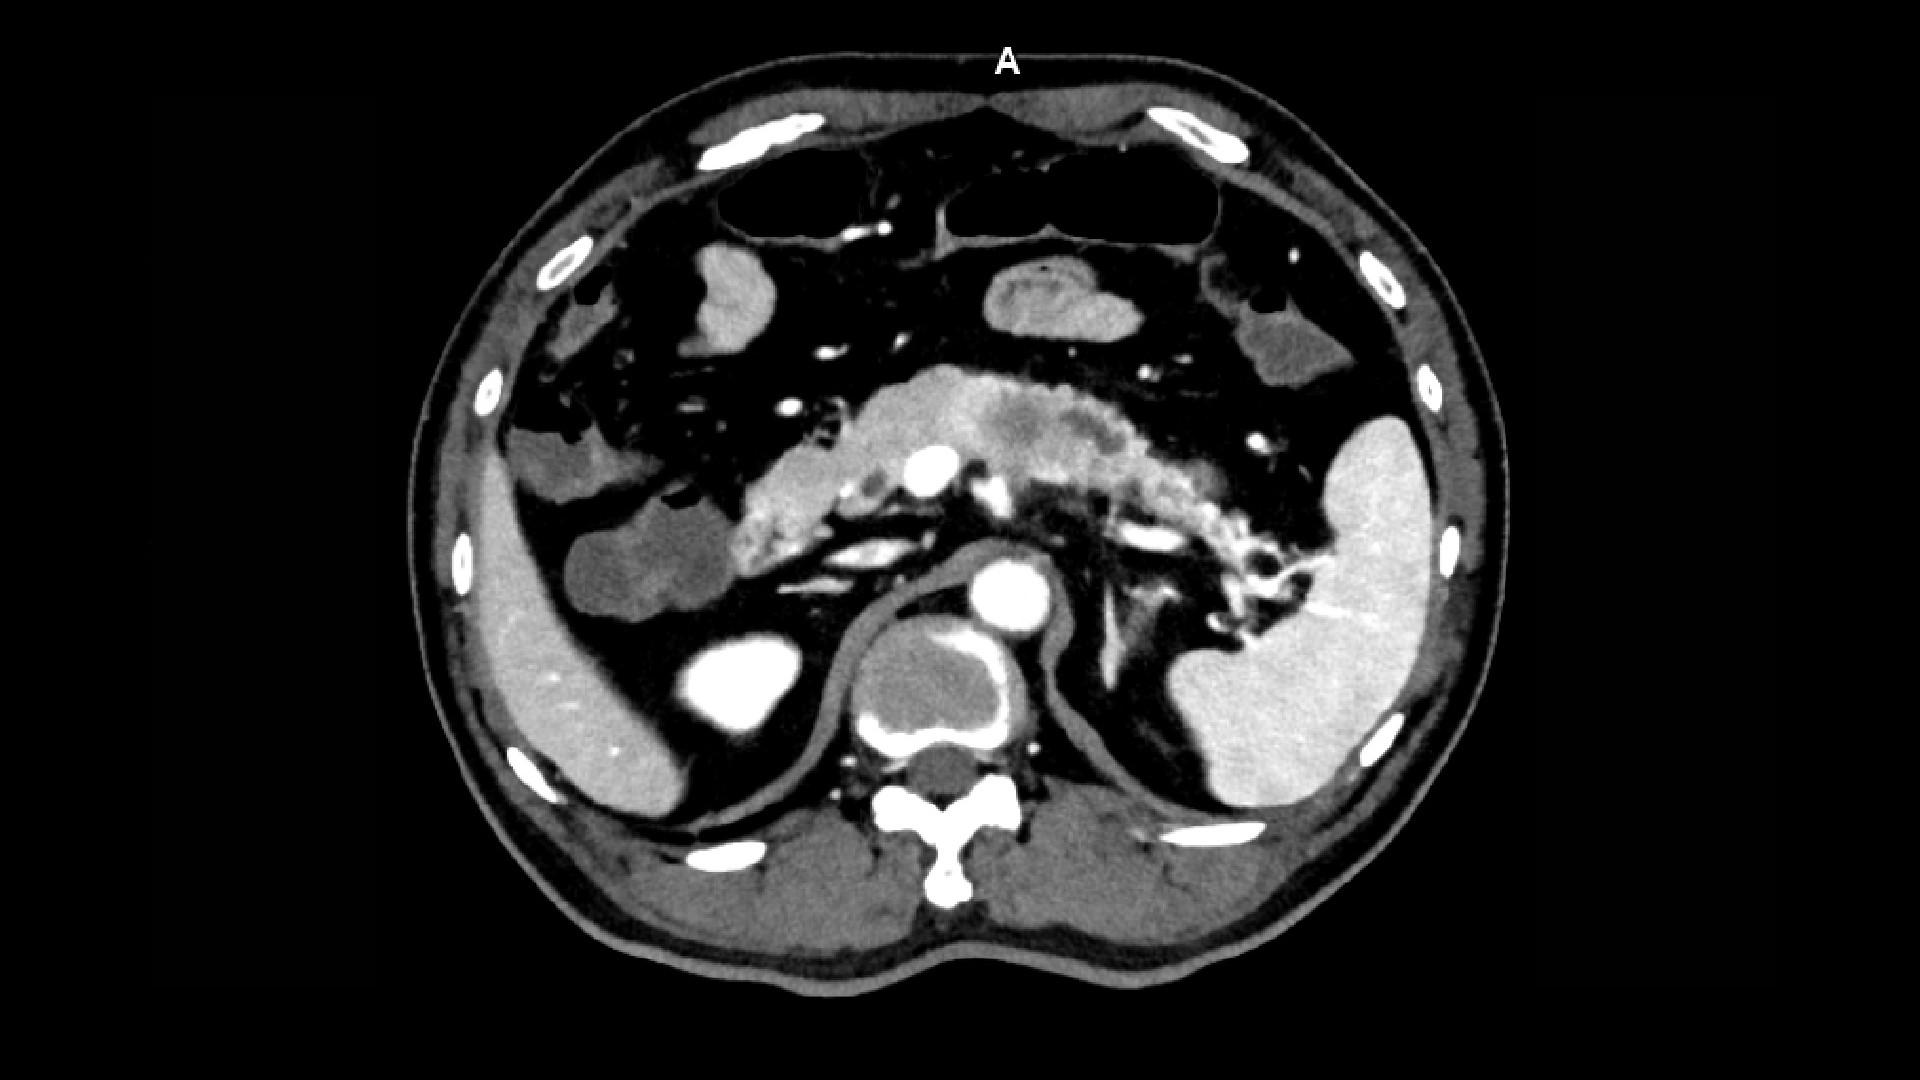

NAEOTOM Alpha and its Quantum Technology are revolutionizing CT use in the field. Stay up to date on all the latest discoveries and highlights from colleagues around the world as they exploit the advantages and potential of its ultra-high resolution, inherent spectral imaging, and clinical insights supporting your diagnostic precision available across a variety of clinical fields. We’re collecting all the highlights as they come in, gathered here in one spot for your convenience. Check in again soon!